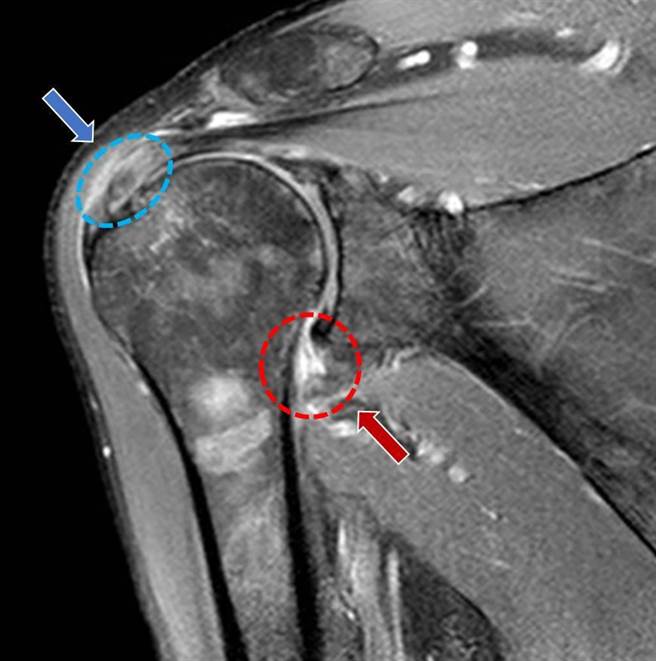

肩膀关节磁振造影检查:上、下箭头所指分别为旋转肌腱发炎处、肩关节囊发炎处。(部苗医院提供/李京升苗栗传真)

卫福部苗栗医院放射科主任徐庸表示,经检查发现龚先生的关节活动度受限,X光检查未显示钙化或关节退化,不过再进一步的超音波和磁振造影检查确认诊断为「旋转肌袖肌腱炎」和「沾黏性肩关节囊炎」。